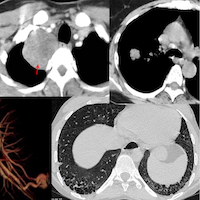

51-yrs old in 2012 presented with a fibrotic NSIP pattern.

The video describes the temporal evolution from 2017 to 2025 with a mixed pattern of fibrotic NSIP, fibrotic OP and DPO/CiOP and a final CTD diagnosis that was established only early this year with evidence of PPF.